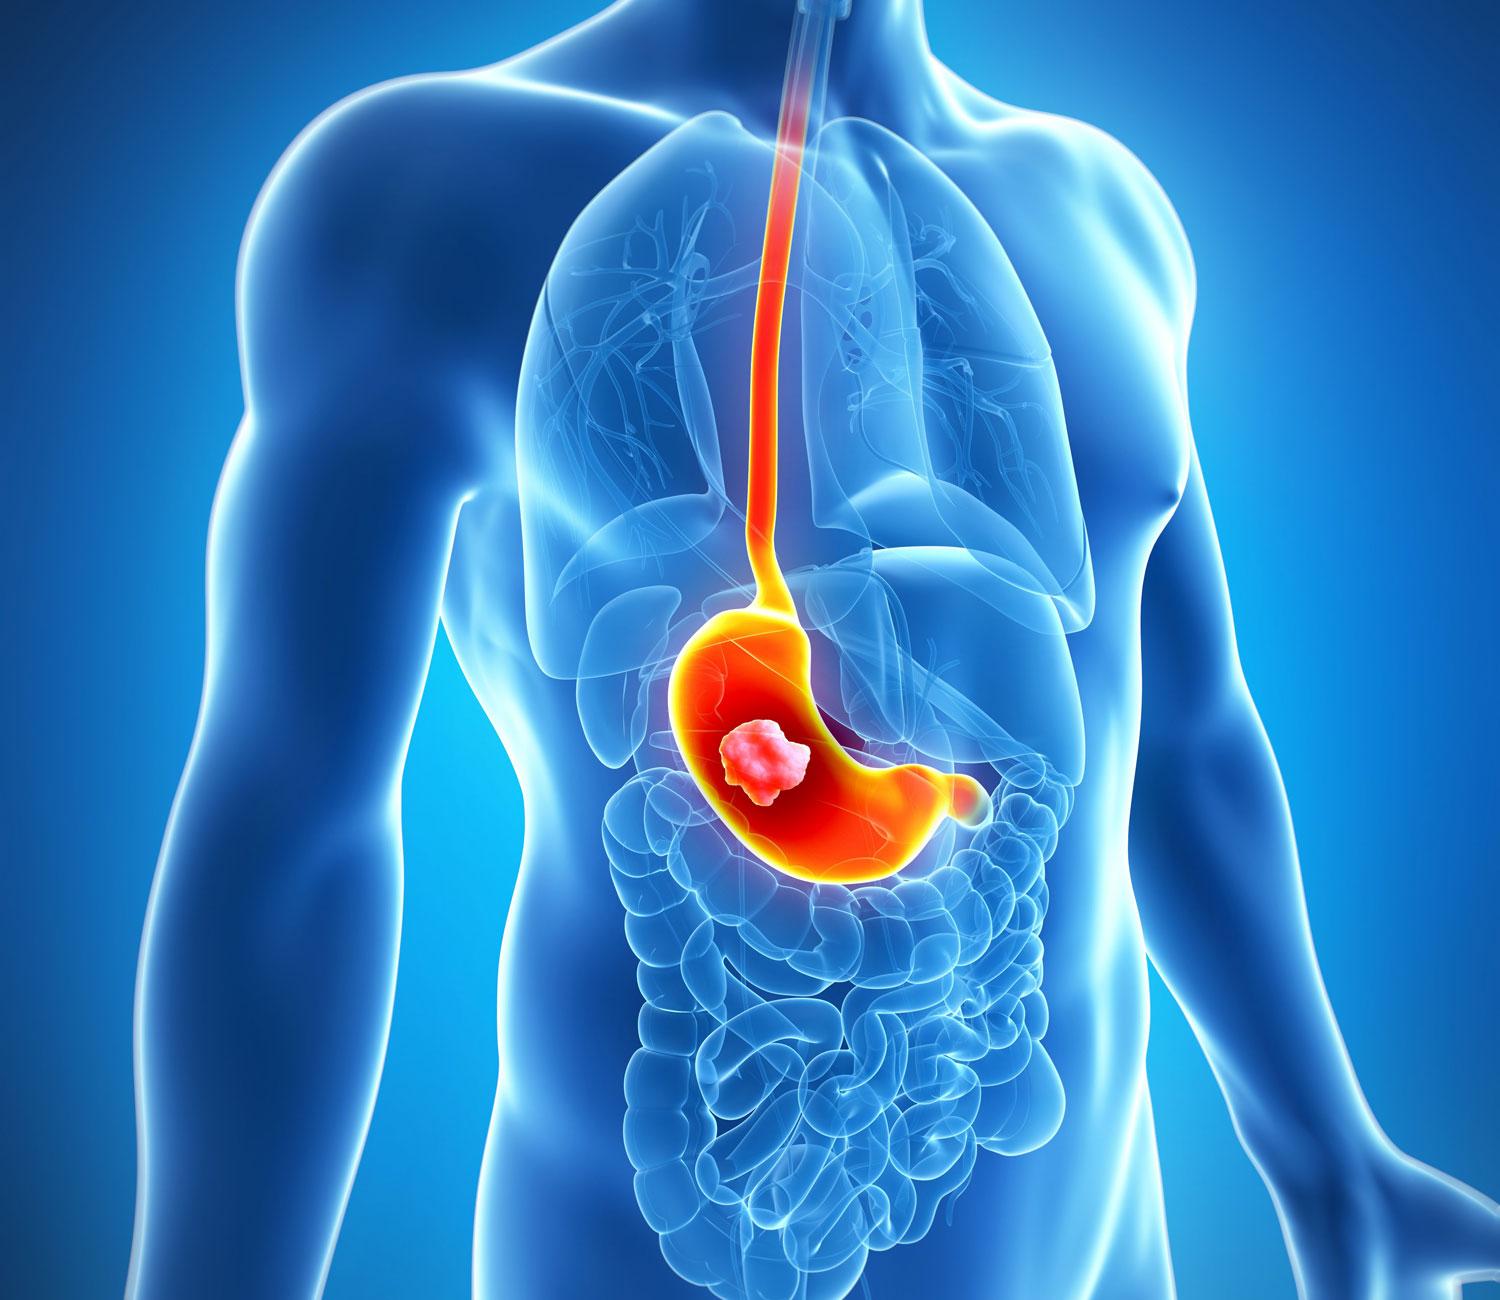

- соляная кислота, способствующая переработке пищи в желудке, выплескивается в пищевод, что приводит к ожогу слизистых. При постоянном ее воздействии, на стенках гортани и пищевода может образоваться раковая опухоль, не говоря уже о том, что придется попрощаться с красивыми зубами, как уже говорилось ранее;

- пища уже покинула организм, а ферменты и желудочный сок, которые помогают ее перевариванию, продолжают выделяться. Желудок и верхние отделы кишечника при этом подвергаются регулярной обработке кислотами, которые предназначены для усвоения продуктов питания. Это приводит к образованию эрозий и язв, а также злокачественных новообразований;